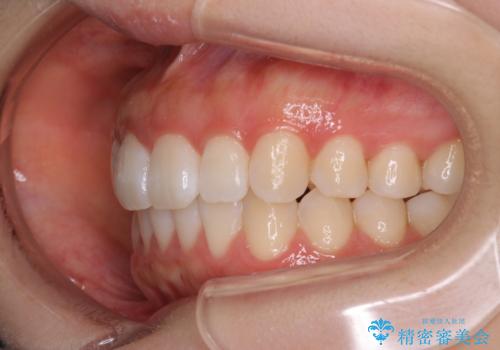

前歯のがたつきをインビザラインで目立たない矯正

- 上下の前歯のがたつきを主訴に来院されました。

マウスピースでの矯正を希望されたので、インビザラインで矯正治療を行うこととしました。

インビザラインではシュミレーションによりどのように歯が動くかを確認して矯正することができるので、患者様も安心して矯正をすることができました。